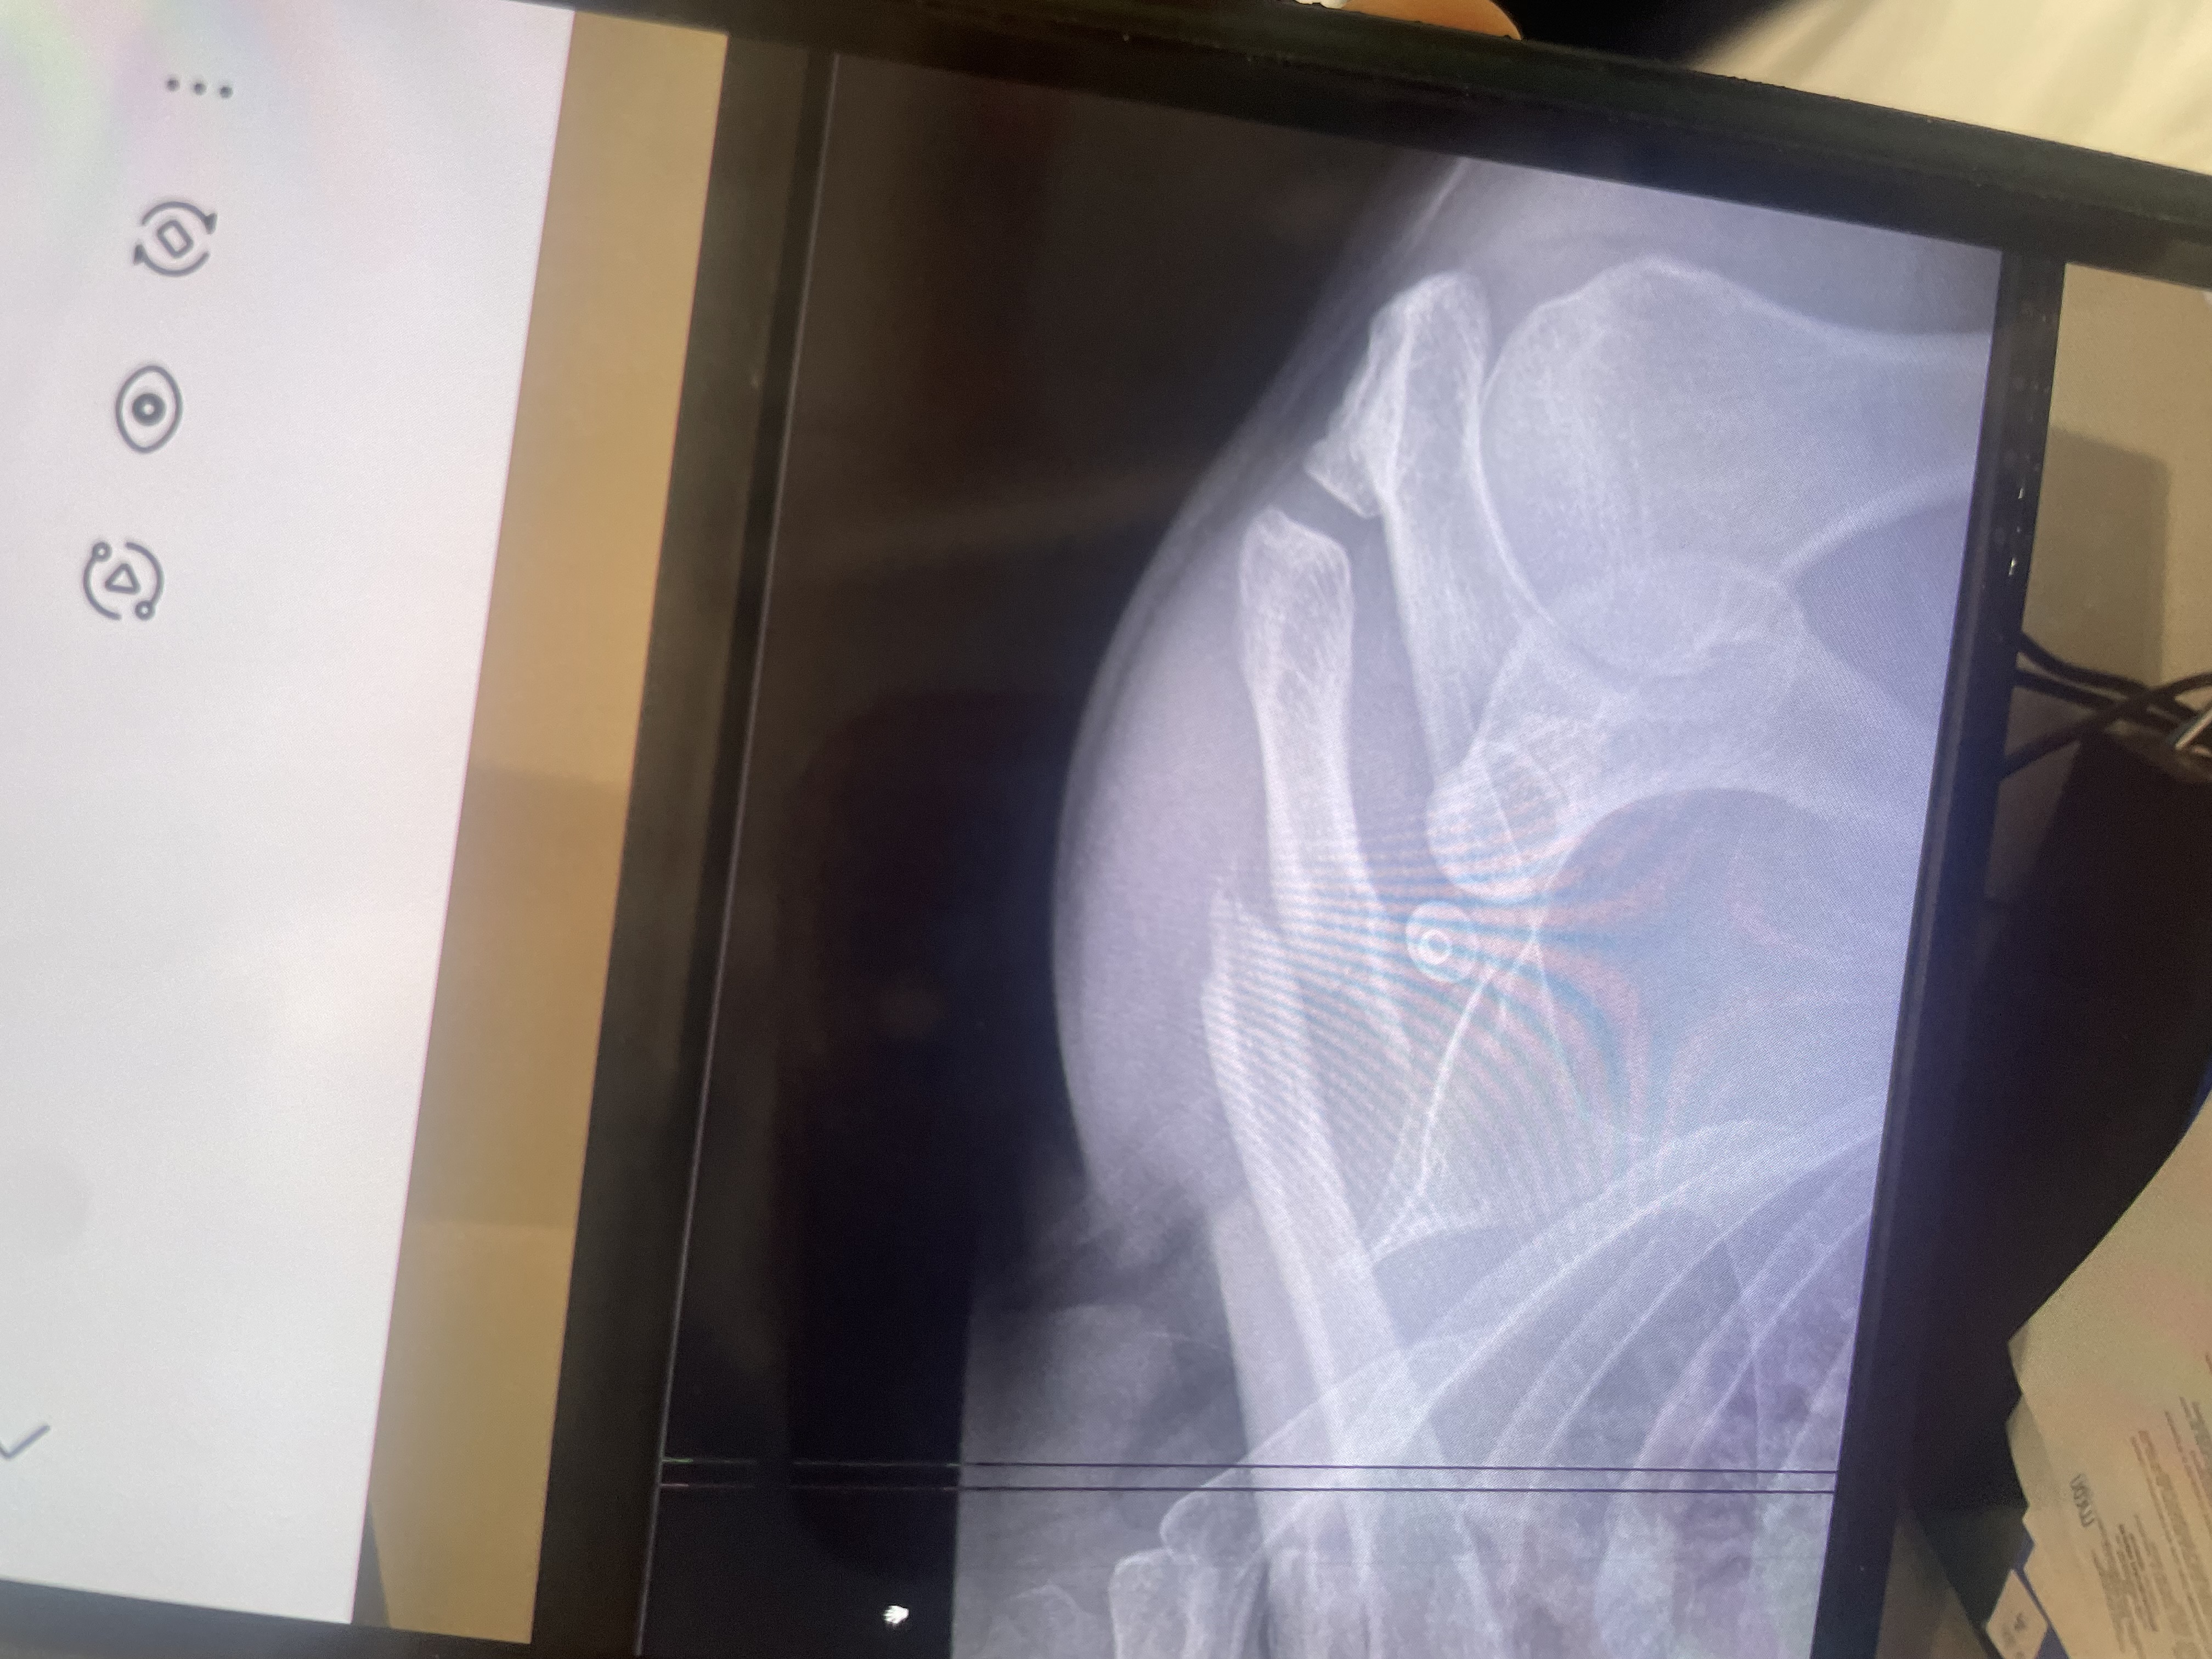

Der Automotodrom Grobnik hat mir einen Schlüsselbeinbruch als Souvenir mit nach Hause gegeben.

IMG_6827.jpeg

Bild 03.06.24 um 10.01.jpeg